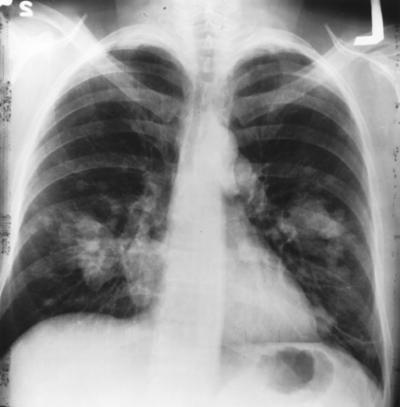

This is an X-ray image of the chest with growth on the left side of the lung.

(Photo Credit: National Cancer Institute)